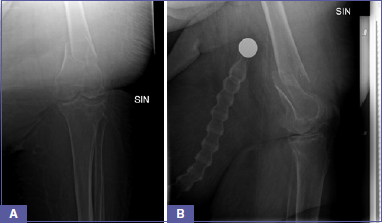

S.O. is a 70-year-old woman who presented to our Emergency Department after falling at home on April 27th, 2022. Our patient presented with a left distal femur fracture (AO classification: 33A3.2) (Fig. 1) associated with severe obesity (height 170 cm, weight 200 kg, and BMI 69.2), diabetes, chronic kidney disease (CKD), and anemia (Hb 9.2 g/dl) most likely caused by the CKD that worsened following the trauma. She was immediately admitted to the Orthopedic Department and underwent a left knee CT scan to further analyze the fracture pattern.

Figure 1.Pre-operative X-ray of the supracondylar femur fracture.

Figure 4.Post-operative X-rays.